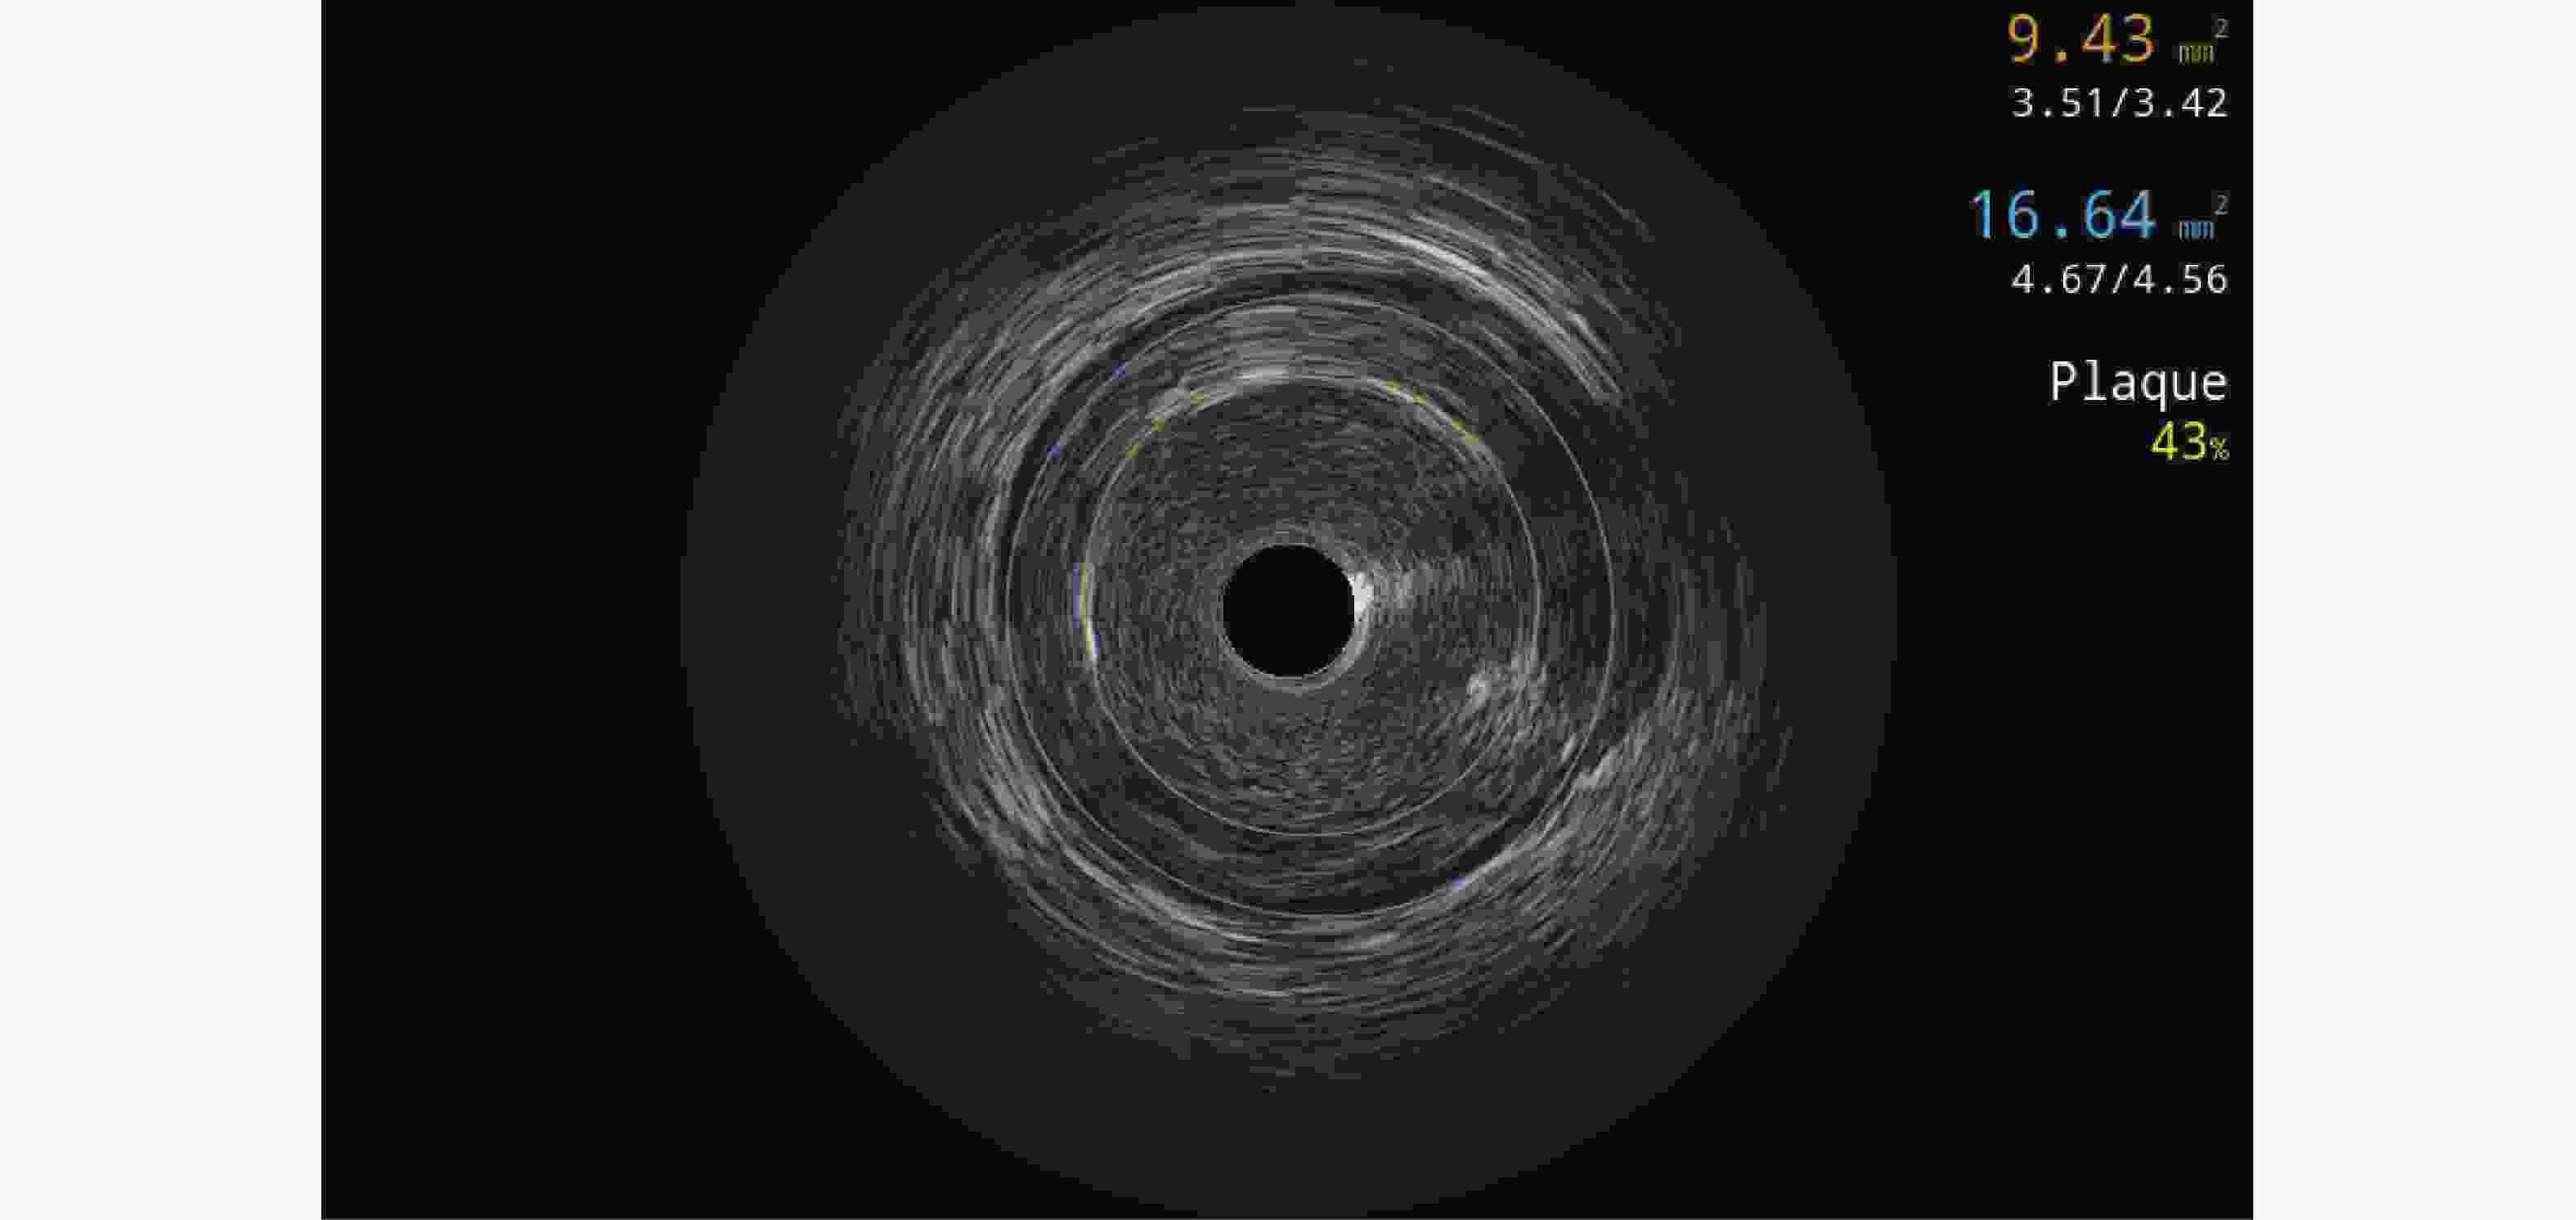

• 图  1  支架术前冠脉血管内超声图像

Figure  1.  Coronary intravascular ultrasound image before stent implantation